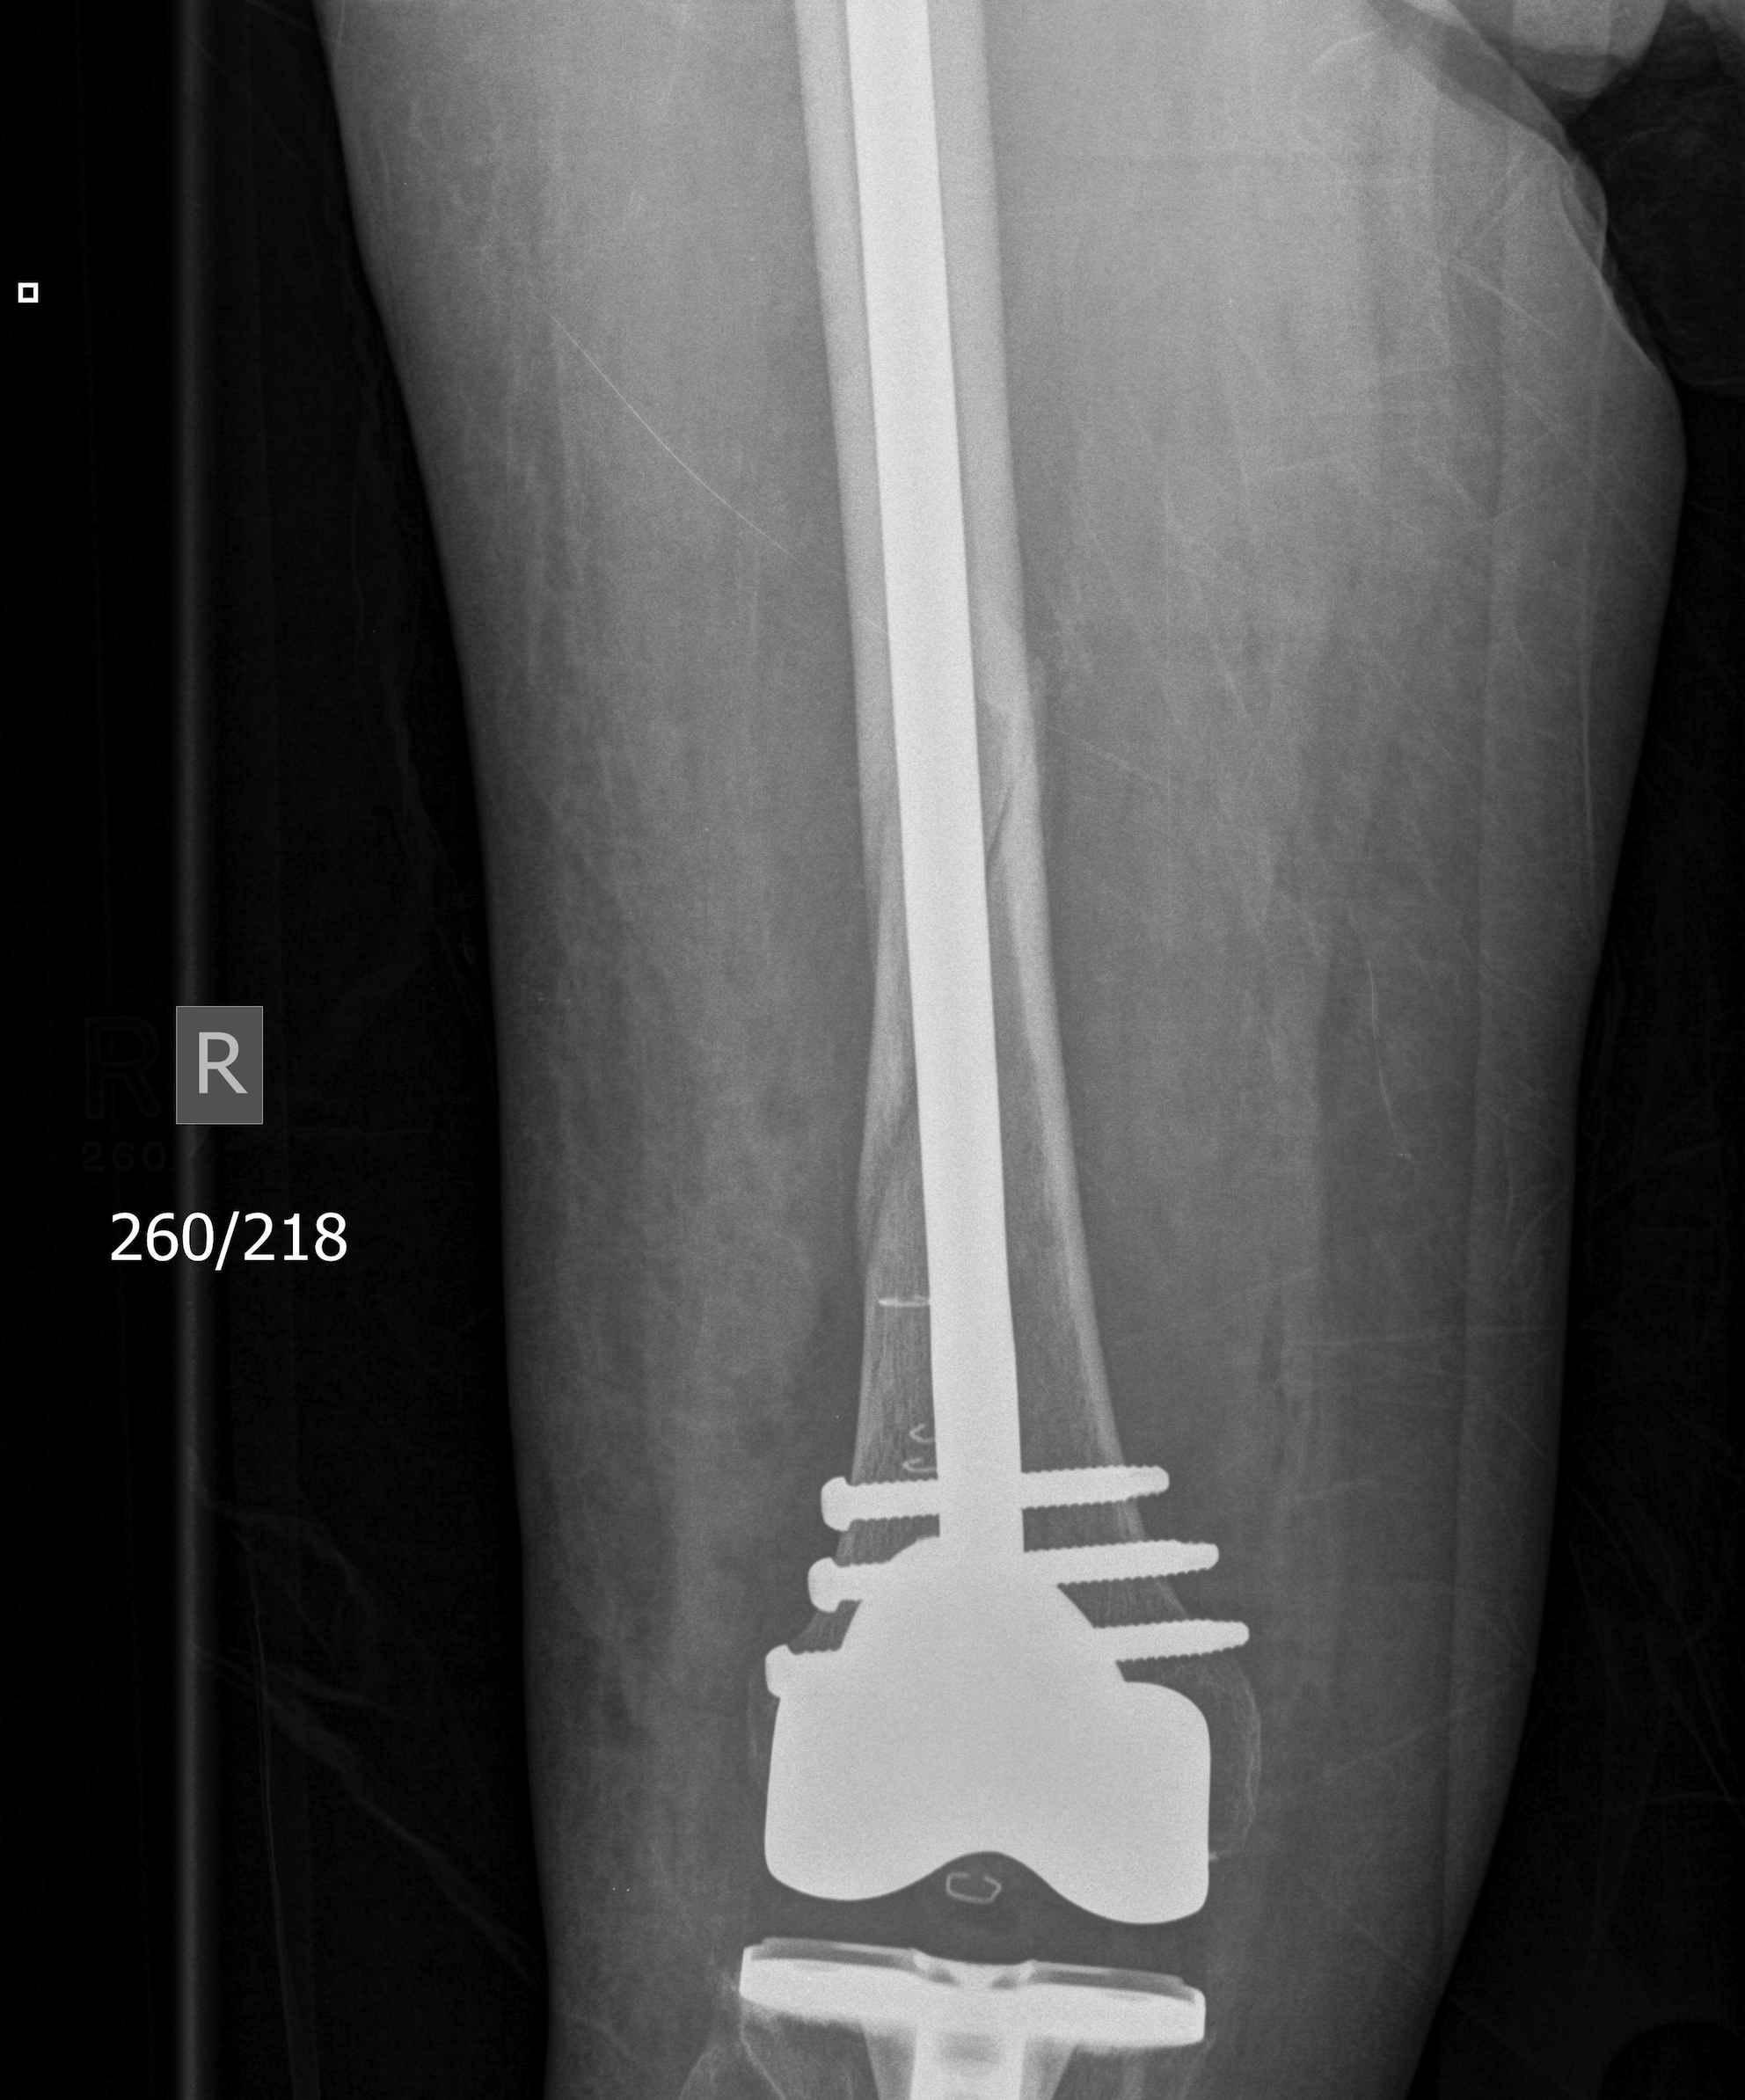

3.  Anterograde nail

Indications

- sufficient bone above implant for distal locking

Issues

- stress riser between femoral implant and nail

- must ensure correct alignment

TKR Femoral FractureTKR Femoral Nail APTKR Femoral Nail Lateral